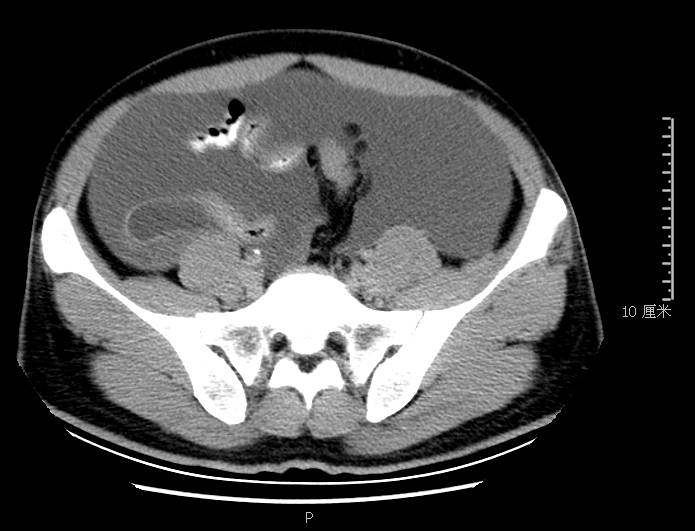

全腹CT:(1)结合病史考虑腹膜炎(见图2A),大量腹水;(2)右骼窝区管状样结构,考虑阑尾扩张(见图2B);(3)肝脏多发小囊肿(见图2C);(4)肝内胆管轻度扩张,建议隔期复查。

本例确诊后对B超及CT再次回顾发现:腹腔、盆腔可见不均质中强回声包块,部分呈囊实状,腹膜增厚,大网膜成饼状(如图2A)和肝周可见不均质中强回声弧形压迹、脾周可见不均质中强回声包饶,肝脏成扇贝样改变(如图2C),但在诊断报告中未提及。有学者发现mantle和scalloping(如图2A,2C)在PMP中具有代表性,且mantle较scalloping更为常见,若mantel征同时伴有大小不一的囊性改变,则更具诊断价值。

图2c肝脏成扇贝样改变(肝脏由于受肿瘤实质性或囊性组织压迫而其实质却未受侵犯,于是在一处或多处呈下凹状或扇形皱褶状(scalloping)